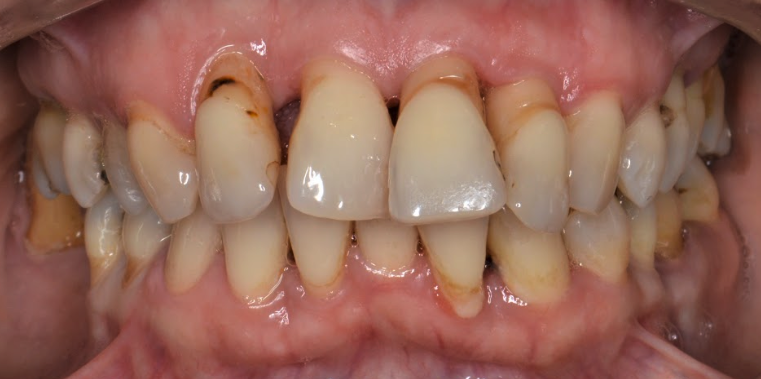

În funcție de faza în care a fost prinsă boala, dacă aceasta este acută sau cronică, dar și în funcție de gravitatea și dimensiunea pungilor parodontale, medicul dumneavoastră vă va recomanda în urma etapei de terapie inițială asocierea unor antibiotice pe o durată cuprinsă între 5 și 14 zile. În cazurile severe, cu retracții mari ale gingiilor și pungi parodontale adânci (Fig. 5.3.2) se poate indica asocierea a 2 antibiotice, pentru a cuprinde un spectru cât mai larg antibacterian. De asemenea, în cazurile refractare la tratament sau în cele recidivante, se va realiza o antibiogramă a secrețiilor parodontale urmată de un tratament medicamentos în funcție de rezultatele acesteia.